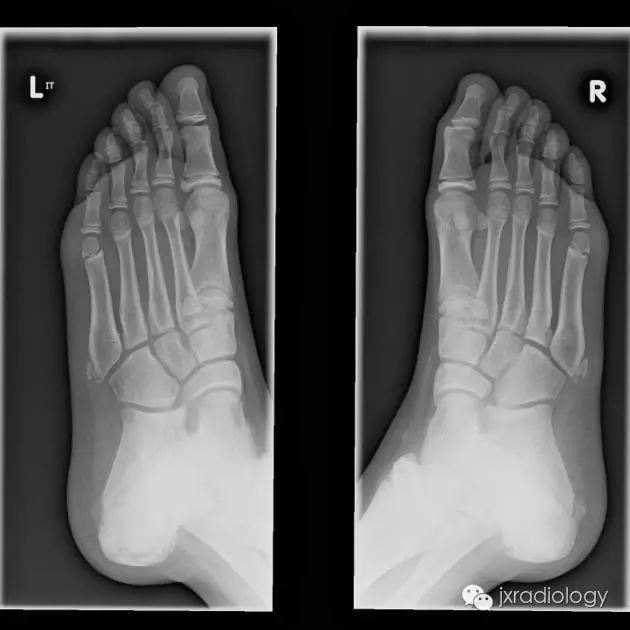

骨骺裂是一种正常变异。它可以是单侧或双侧,最常见的部位是足的第1趾近节趾骨的骨骺。

X线平片显示骨骺见透亮状裂隙影;透亮影的边缘是可变的,可能是锐利的或不规则的。骨骺裂可保留至生长板的融合。

骨骺裂必须和骨折鉴别。一般骨折损伤2-3周后复查平片可见愈合的迹象。识别这个现象是重要的,以避免过度治疗和不必要的手术干预。

A cleft epiphysis has to be differentiated from fracture. Generally fractures demonstrate signs of healing if the radiograph is repeated 2-3 weeks after injury. Recognition of this entity is important to avoid over treatment and unnecessary surgical intervention.

病例图片:骨骺裂